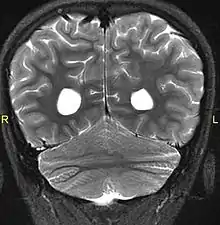

Aside from the physical characteristics of the eyes there is also less sensation in the eyes when stimulated.[4] The eyes also show low motor control (ataxia).[4] Along with ataxia comes a lack of coordination or ability to judge the distance of objects (dysmetria).[6] MRIs show a constant feature of rhombencephalosynapsis–a condition marked by the absence or partial absence of the cerebellar vermis and varying degrees of fusion in the cerebellum in every case of Gómez–López-Hernández syndrome.[4][7][8] Also absent are the trigeminal nerve of the trigeminal cave and the foramen rotundum, causing abnormal sensations on the forehead and the corneas.[6][8] One Gómez–López-Hernández syndrome case in Japan also presents fever-induced seizures.[9] Others may or may not present with non-fever-induced seizures.[4] Malformations of motor centers in the brain cause reduced muscle strength (hypotonia).[8] Eleven of fifteen people in one study showed moderate-to-severe intellectual disability.[6] In cases where it has been noted, head nodding is present.[6] Hydrocephalus and enlargement of the ventricular system is consistently present.[6] A reduced corpus callosum is present in some cases (agenesis of the corpus callosum).[6]

MRI showing fusion of cerebellar hemispheres common in GLH syndrome